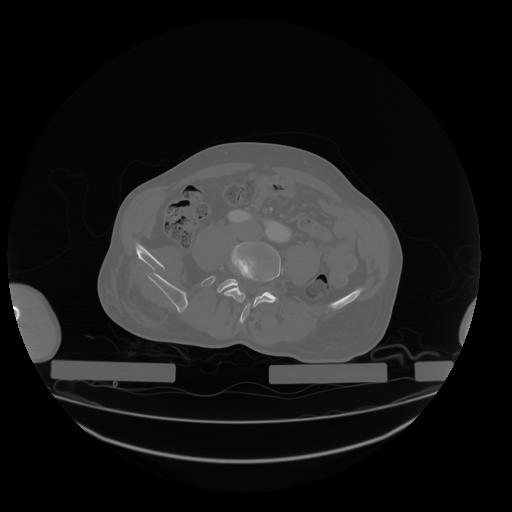

28 CUERPO,CE,Vol,2.0,CUERPO,,